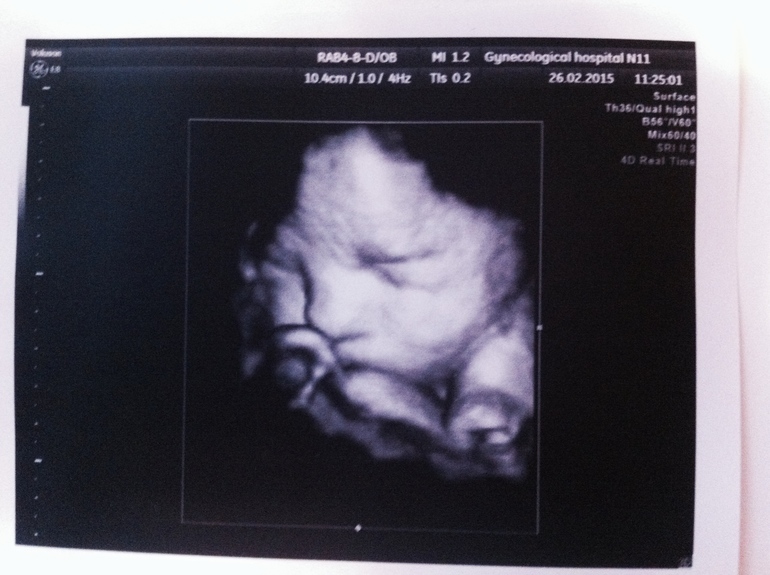

Больше всего меня в тот день обрадовало, что показали личико моего маленького)

К стати, УЗИ делала в 11 гинекологической больнице, очень понравилось все) И женщины в регистратуре (очень доброжелательные, после узи даже спросили, как дела)) искренне порадовались), и врач Узи Лейчик очень грамотно все рассказал, показал, пошутил даже)